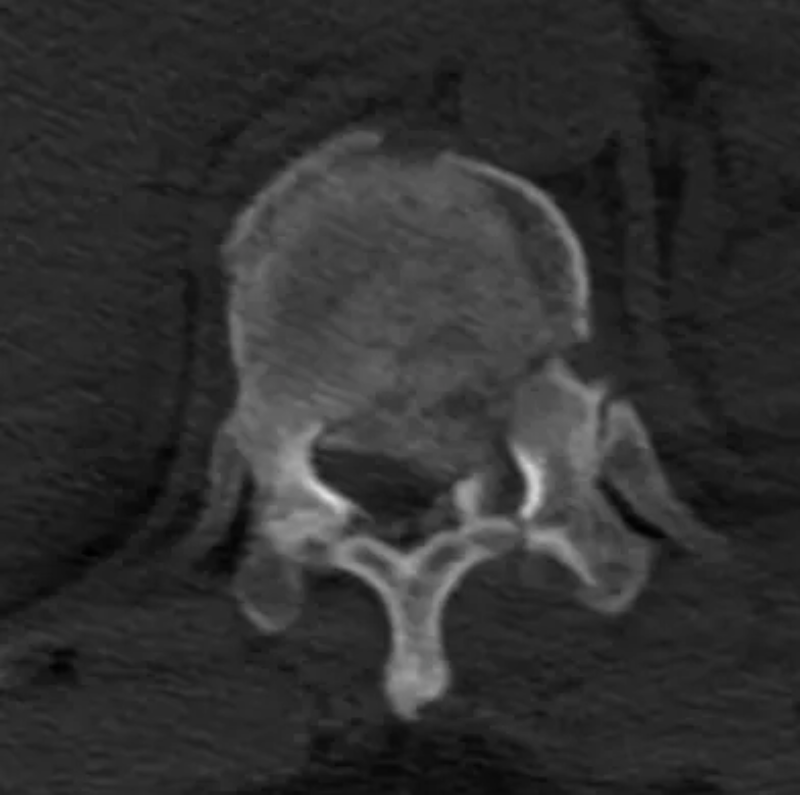

△胸4椎體爆裂性骨折伴脫位。

胸12椎體爆裂性骨折,骨折碎塊壓迫椎管。